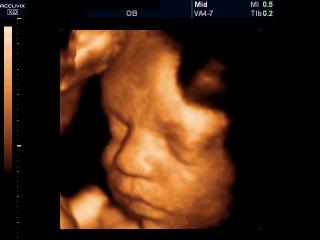

Fetal face, 3D

Accuvix-XQ. Fetal face, 3D.